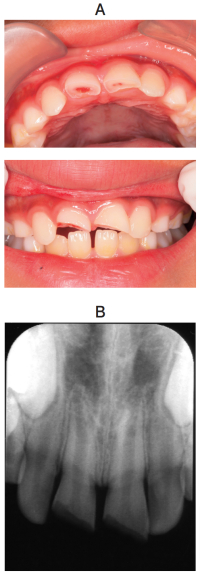

8歳の女児。歯の破折を主訴として来院した。1時間前に転倒し顔面を強打したという。歯以外に受傷部はなく意識も明瞭である。両側の上顎中切歯の動揺は生理的範囲であり、打診痛はあるが自発痛はない。1⏌は生活歯髄切断、⎿1 は直接覆髄を行った。初診時の口腔内写真とエックス線写真を別に示す。

1⏊1 に対する治療法の違いの根拠はどれか。1つ選べ。